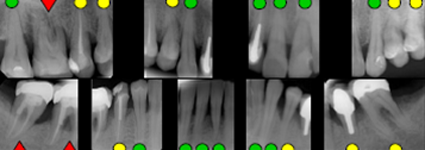

Periometr - první plně automatizovaný přístroj pro zjištění periodontálního statusu pacienta - diagnózy, léčby a profylaxe parodontitidy a dalších onemocnění. Díky správnému určení periodontálnímu statusu pacienta lze včas odhalit a minimalizovat objevující se obtíže.